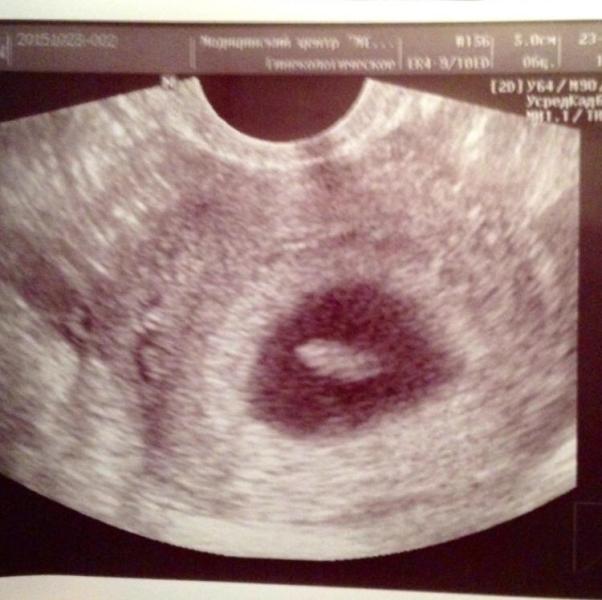

12 недель и 3 дня , 1 скрининг на УЗИ тьфу тьфу тьфу все хорошо 👌🏻 плод развивается согласно сроку ))

А ещё я почему то уверенна была что у нас девочка , а на УЗИ показали мальчик 👶 но сказали что так как срок не большой это ещё не точно , хотя пипетку по моему отчётливо видно 🙈😂 ну или может это не она ?